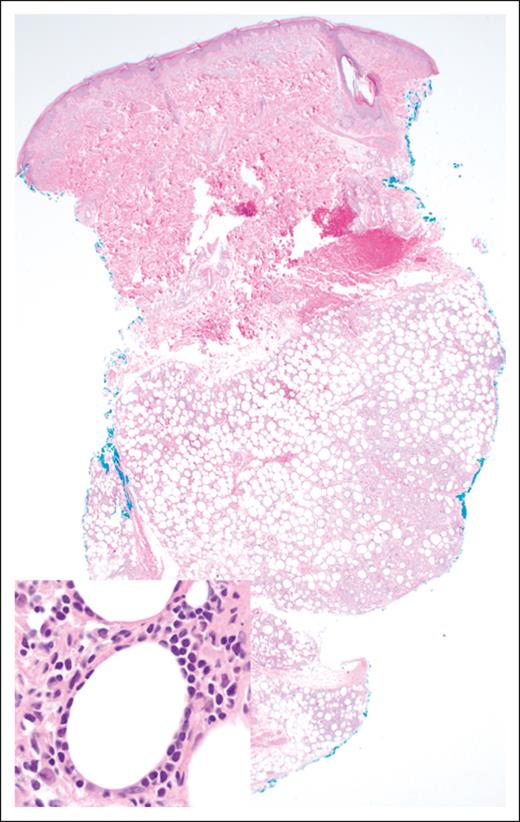

The histopathologic features of EATLs are highly variable. The neoplastic lymphocytes are generally medium to large in size and show varying degrees of pleomorphism, with some cases displaying immunoblastic or anaplastic cytomorphology.17 The tumors are frequently accompanied by a mixed inflammatory infiltrate composed of histiocytes, eosinophils, and plasma cells, which may obscure the malignant cells (Figure 1). Portions of small intestine away from the tumor mass frequently show typical histopathologic features of celiac disease.18 EATLs typically express cytoplasmic CD3, CD2, CD7, CD103, and cytotoxic markers (TIA-1, perforin, and granzyme-B) and lack CD4, CD5, and CD56 expression. Most cases do not express surface CD3 and TCR. Approximately one-third of patients are CD8+18-20 and intracellular TCRβ expression is detected in one-quarter of patients.21 CD30 expression is common in patients exhibiting anaplastic morphology, but ALK-1 is always negative,17 and the neoplastic T cells are negative for Epstein-Barr virus (EBV).

EATL. (A) Clusters of pleomorphic lymphoma cells reside within a mixed inflammatory background, focally infiltrating the small intestinal epithelium (original magnification, ×500; hematoxylin and eosin [H&E] stain). (B) The large intestine contains a sheet-like proliferation within the lamina propria (original magnification, ×400; H&E stain).

SPTCL. The lobular subcutaneous infiltrate spares the overlying dermis and epidermis (original magnification ×20; H&E stain). Inset: the lymphoma cells display a characteristic rimming pattern around adipocytes (original magnification ×500; H&E stain).